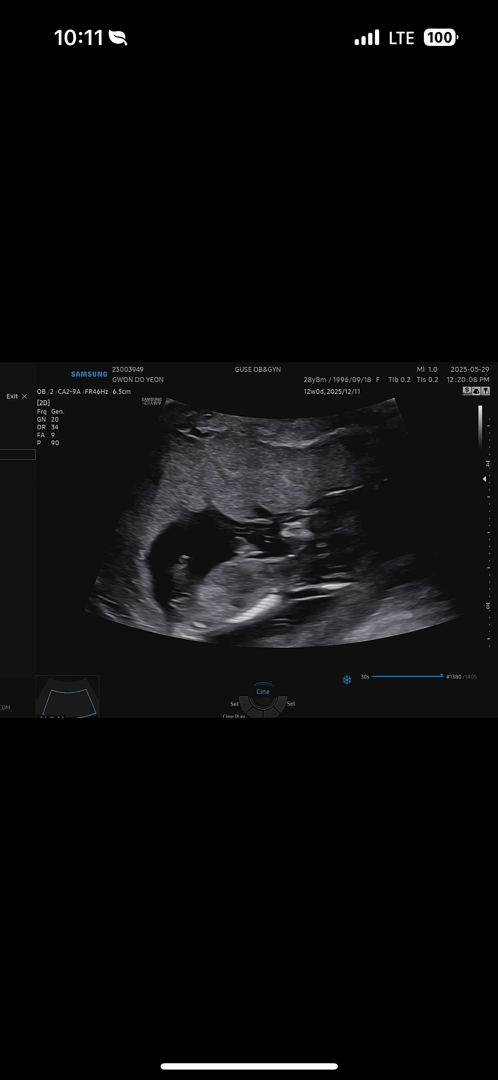

각도법 봐주세요 12주차 사진입니다 !

딸일까요? 아들일까요 ? 😂

추가사진입니다 !